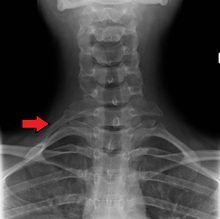

Variations in the number of ribs occur. About 1 in 200-500 people have an additional cervical rib, and there is a female predominance.[7] Intrathoracic supernumerary ribs are extremely rare.[8] Bifid or bifurcated ribs, in which the sternal end of the rib is cleaved in two, is a congenital abnormality occurring in about 1.2% of the population. The rib remnant of the 7th cervical vertebra on one or both sides is occasionally replaced by a free extra rib called a cervical rib, which can mechanically interfere with the nerves (brachial plexus) going to the arm.